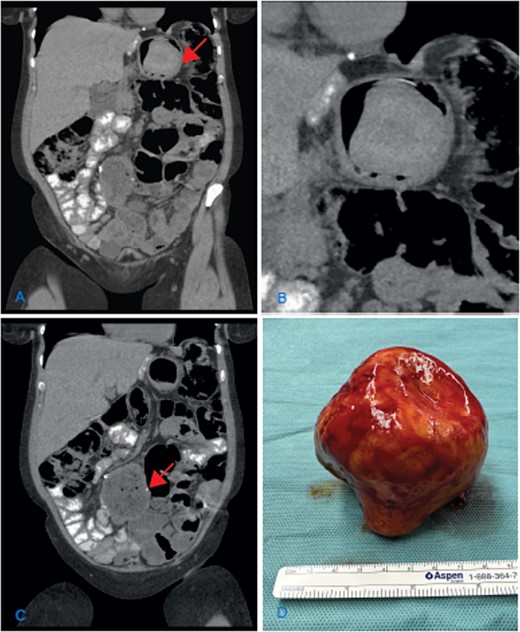

The clinical examination and lab results were normal. A gastroscopy did not reveal any pathological findings. The abdominal CT scan showed dilation of the jejuno-jejunostomy (JJ), biliopancreatic limb, and gastric remnant (Fig. 1A and C). Within the gastric remnant, hypodense mass of at least 5-cm diameter was detected (Fig. 1B). Considering the imaging findings, the patient was proposed for revisional surgery.

(A) Coronal CT scan image showing the dilatation of the gastric remnant with hypodensemass (arrow); (B) zoom of the gastric remnant with a 5-cm hypodense mass; (C) coronal CT scan image of the dilated JJ-anastomosis (arrow); (D) retrieved specimen a gallstone with approximately 10-cm diameter.

An elective laparotomy was performed. By palpation of the gastric remnant, a hard mass was detected. The specimen was retrieved through a gastrotomy. A hard yellow-brown stone ~10 cm in diameter was found intraluminally. After retrieving the intraluminal mass, the dilated side-to-side JJ-anastomosis was resected and reconstructed in an end-to-side fashion.

The chemical analysis confirmed the macroscopic suspicion of a cholesterol gallstone (Fig. 1D). The follow-up was uneventful, and the symptoms resolved.